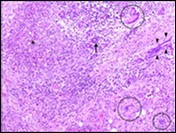

Core needle biopsy of idiopathic granulomatous mastitis enunciates multiple aggregates of non- caseating epitheloid cell granulomas within and encompassing breast lobules, constituted of epitheloid histiocytes, lymphocytes, neutrophils and multinucleated giant cells. Granulomatous inflammation is predominantly lobulo-centric. The inflammation is preponderantly composed of lymphocytes, plasma cells, epitheloid histiocytes, multinucleated giant cells and neutrophils. Neutrophils can configure micro-abscesses and encompass vacant micro-cystic cavities, morphological features which are in common with cystic neutrophilic granulomatous mastitis. Non specific lobulitis along with a lymphoid and plasma cell infiltrate accompanies the granulomatous inflammation. Necrosis is usually absent. Neutrophilic micro-abscesses can be accompanied by fistula formation 4, 5.

Multinucleated giant cells are detected in an estimated three fourths (78.5%) instances. Plasma cells are discernible in around half (53.9%) of the subjects and usually appear at the margins of cystic vacuoles with centric accumulation of neutrophils within the granulomas.

Figure 3.Granulomatous mastitis with scattered langhans and foreign body giant cells, epitheloid cell granuloma and lymphoid ingress11.

Figure 4.Granulomatous mastitis with epitheloid cell granuloma, langhans and foreign body giant cells with lymphocytic rimming12.